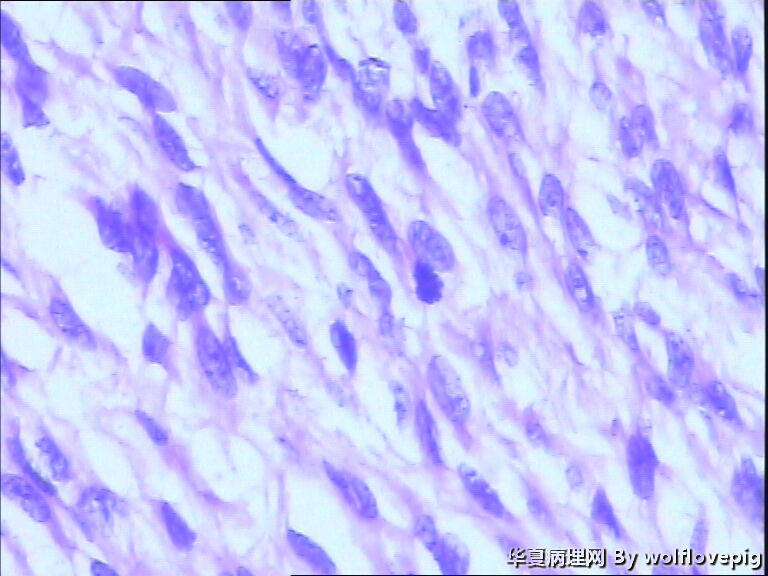

37y,肌壁间可见多个小结节0.2~0.8cm。

图2